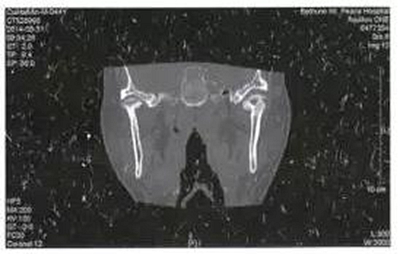

病例4,男,44歲。因左側(cè)耳前反復(fù)腫痛6月就診,檢查左側(cè)耳前區(qū)壓痛,軟組織腫脹不明顯,未見(jiàn)瘺管形成,張口度30mm,張口不偏斜,咬合關(guān)系可??趦?nèi)檢查未見(jiàn)病灶牙,無(wú)瘺管形成。全頜曲面斷層片檢查未見(jiàn)埋伏牙齒、囊腫等可能引起感染的病灶。CT掃描顯示左側(cè)髁突關(guān)節(jié)面成蟲(chóng)蝕樣破壞,中央部分為低密度病變(圖4)。

圖4左側(cè)髁突骨髓炎,關(guān)節(jié)面蟲(chóng)蝕樣破壞